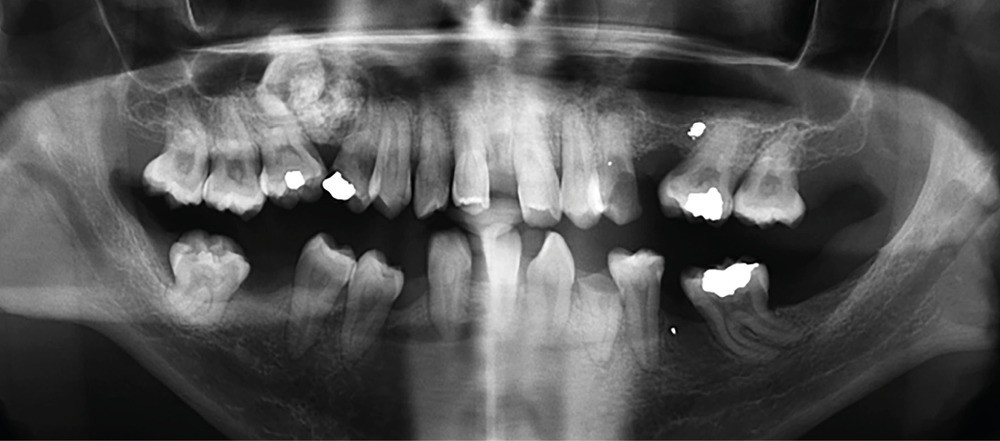

• Radiographie : on observe habituellement une lésion uniloculaire radioclaire bien définie, évoquant une lésion kystique [3]. La topographie de la lésion est plus fréquemment la région mandibulaire antérieure (65 % des cas).

La lésion est fréquemment associée à des odontomes (environ 25 % des cas), des dents incluses et, parfois, des résorptions radiculaires.

Avec le « vieillissement » de la lésion, des calcifications irrégulières ou de densité dentaire apparaissent dans la…